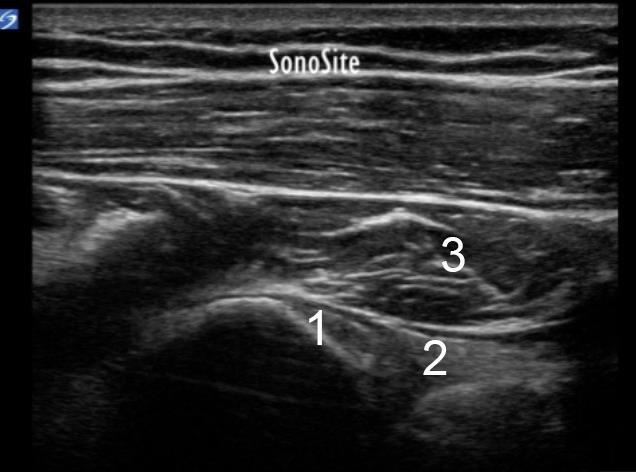

Shoulder Anatomy Teres Minor Evaluation Transverse Axis Mid-Near Myotendinous Junction Image

1. Inferior Glenoid Tubercle (origin of the triceps tendon long head)

2. Triceps Long Head

3. Teres Minor Muscle